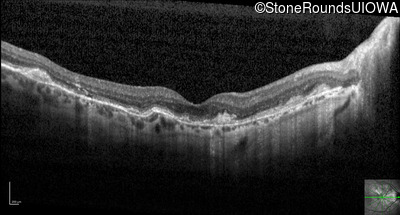

Optical Coherence Tomography - Right - 20/20 -1

Exemplar / OCT Stack

OCT Stack